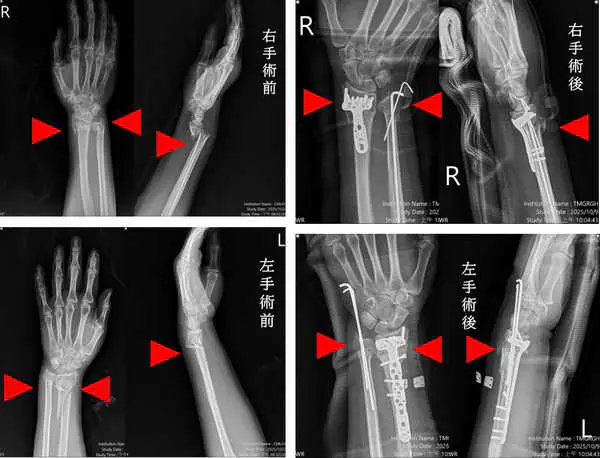

圖說三:患者手術治療前與治療後。